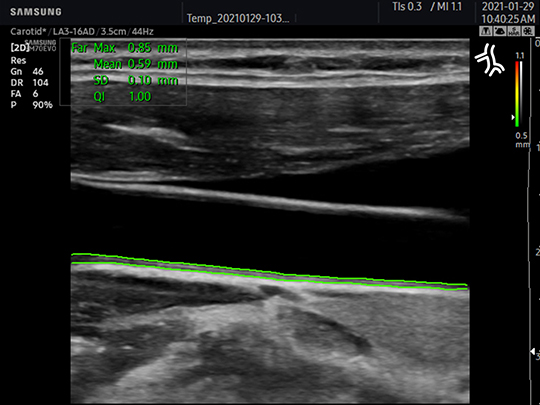

LA3-16AD

- Application: small parts, vascular, musculoskeletal, abdomen, obstetrics, gynecology, pediatric